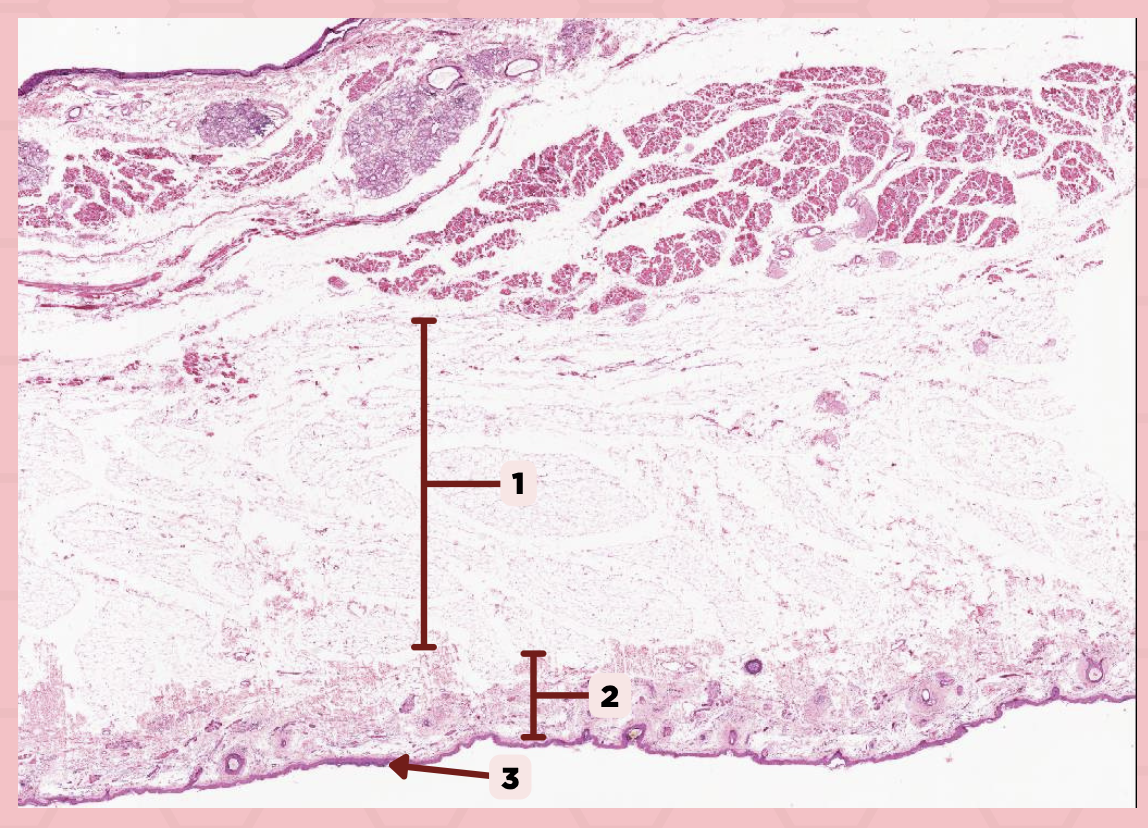

Lip

What specimen is showed in the picture?

Labial Glands (in the Mucosa)

Identify the structure labeled as 1.

Skeletal Muscle Cells

Identify the structure labeled as 2.

Lamina Propria

Identify the structure labeled as 3.

Mucosa

Identify the structure labeled as 4.

Lip

What specimen is showed in the picture?

Skeletal Muscle Fibers

Identify the structure labeled as 1.

Labial Glands

Identify the structure labeled as 2.